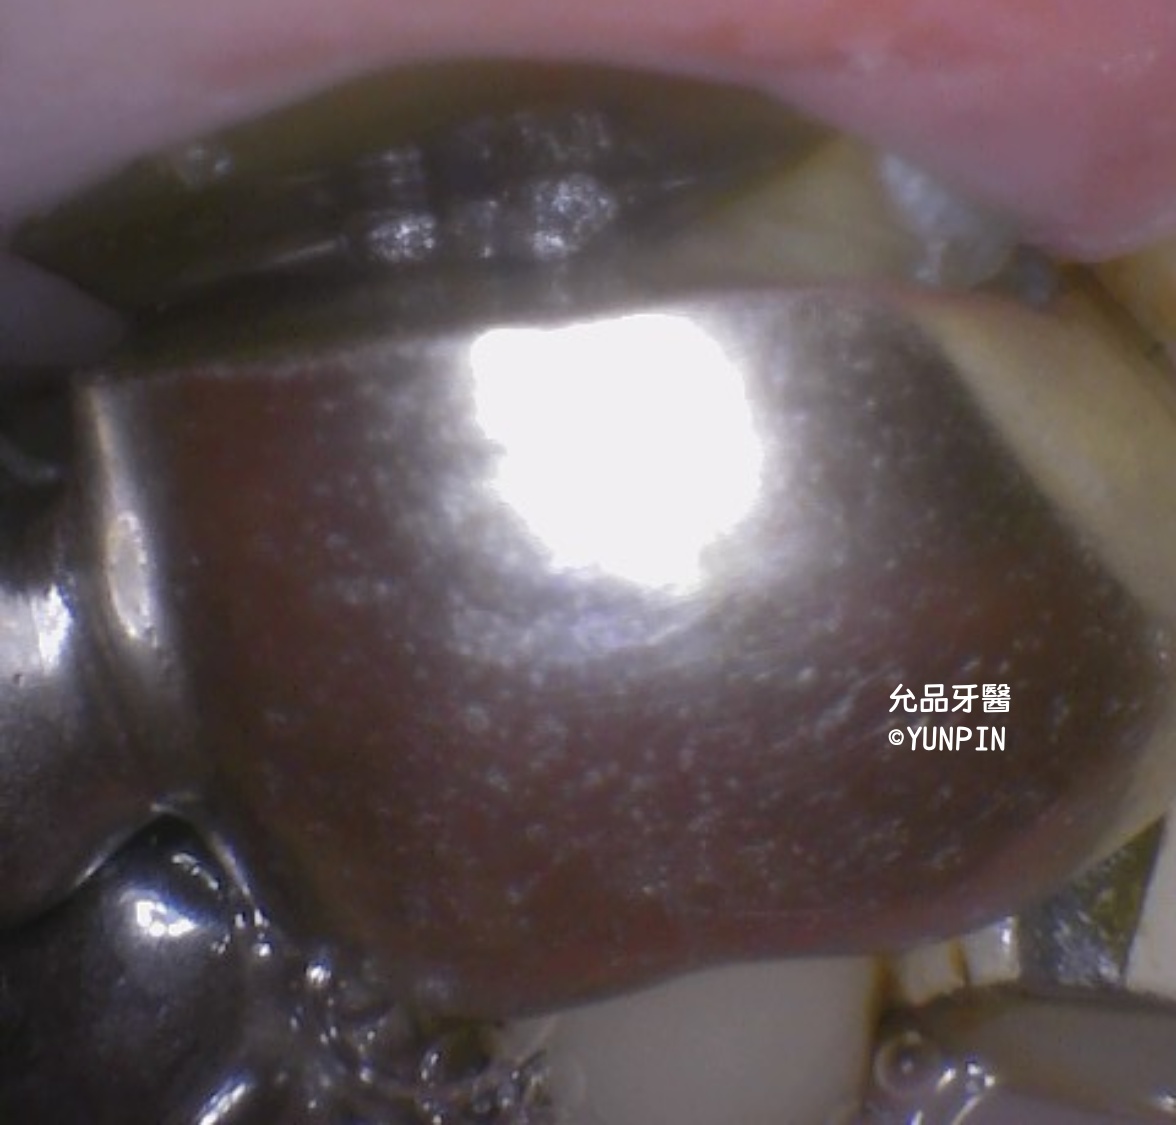

牙套下邊緣不合

拆除牙套後內部蛀牙情況